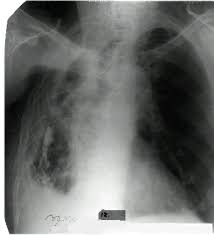

Яки з наведених рентгенограм відповідає спонтанному пневмотораксу.